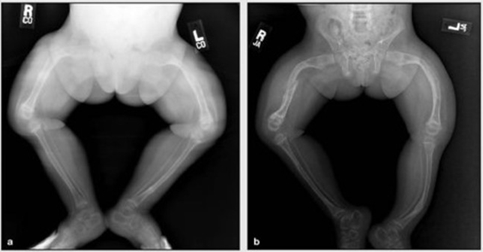

Mang trong mình di chứng của chất độc da cam và căn bệnh xương thủy tinh quái ác, nhưng Huỳnh Thanh Thảo chưa bao giờ cảm thấy tự ti, mặc cảm hay oán trách số phận. Với Thảo, khuyết tật chỉ bất tiện chứ không phải là bất hạnh. Thảo luôn yêu đời, yêu người, lạc quan và sống tận hiến…

Mắc chứng xương thủy tinh từ khi mới lọt lòng nên cuộc sống của chị Đinh Thị Bích Hậu (SN 1974, trú tại khu phố 2, phố Hoàng Diệu, phường Cẩm Thượng, TP Hải Dương) phải chịu quá nhiều thiệt thòi.

Bị mắc bệnh xương thủy tinh từ khi mới sinh ra nhưng cậu bé Lê Anh Xuân (15 tuổi, ở thôn Phú Nhơn, xã Cát Trinh, huyện Phù Cát, tỉnh Bình Định) rất mê đọc, mê viết và ao ước trở thành một nhà văn. Mới đây, ước mơ ấy đã trở thành sự thật. Và dù nét chữ chưa thật tròn, song những giờ phút nghiêng mình trên giường, uốn tay theo trang giấy là lúc Xuân thấy vui vẻ nhất.

Nhìn xương con mềm như cọng rau muống, gãy không biết bao nhiêu lần khiến vợ chồng chị Tâm đau thấu ruột. Lo lắng sau này cha mẹ già yếu, không ai chăm sóc, nâng niu liệu Nga có chống chọi được với nỗi đau "xương thủy tinh"? Suy nghĩ mãi, cuối cùng vợ chồng chị Tâm quyết định sinh thêm một lần nữa, xem như thử vận may với cuộc đời. Niềm mong mỏi duy nhất là đứa con sau này sẽ khỏe mạnh để thay cha mẹ chăm sóc chị của nó. Nhưng niềm hy vọng cuối cùng sụp đổ khi bác sĩ thông báo bé Thanh Ngân cũng bị mắc bệnh "xương thủy tinh".